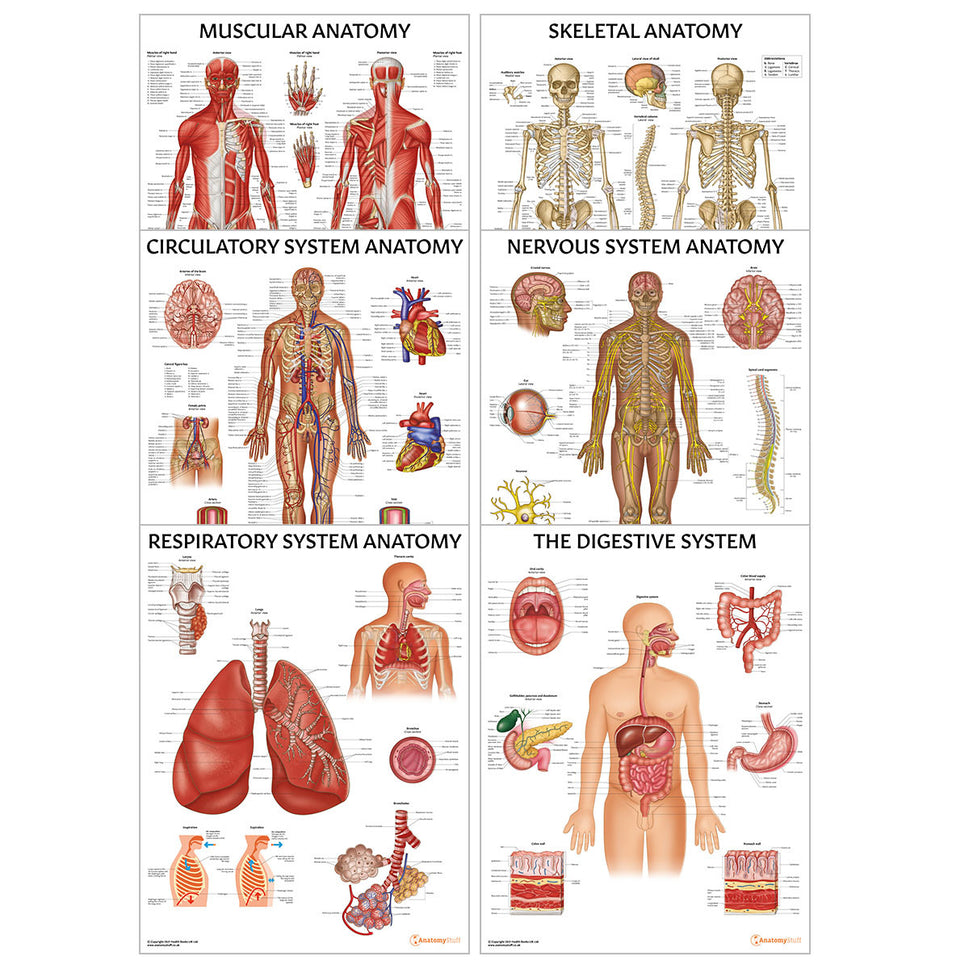

Enhance medical education with our collection of digestive system anatomical models including the stomach, liver, gallbladder, pancreas & colon models. Discover the anatomy of healthy organs as well as common gastrointestinal diseases such as stomach ulcers, gallstones and liver cirrhosis. Our digestive system anatomy posters are ideal for study and patient education.

At AnatomyStuff we stock a diverse range of digestive system anatomical models to suit your training needs. From budget models and affordable medical education posters to highly advanced 3D printed bowel models, you can transform medical training and patient education. As well as our own exclusive collection, we are proud resellers of 3B Scientific, Anatomy Lab, Denoyer-Geppert Science Company, ESP Models, Erler Zimmer and GPI Anatomicals. Explore our exclusive collection of digestive system anatomy charts, posters, fine art prints and digital anatomy study guides. Discover the anatomy of key organs like the liver, stomach, pancreas and bowel as well as the pathophysiology of common conditions like peptic ulcer disease, coeliac disease, IBD and much more. We have anatomy posters suitable for school children all the way up to medical degree level. From a liver anatomy poster to a digital study guide all about common GI disorders, find exactly what you need right here to enhance medical training and patient education.